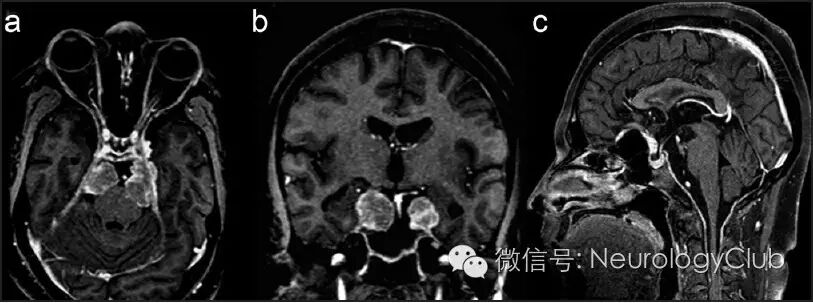

21岁男性,表现为进行性头痛,行走困难和视力、听力下降6年。查体发现患者双侧继发性视神经萎缩,双侧感音神经性耳聋和痉挛性四肢瘫痪。头颅MRI可见中和后颅窝多发结节样病灶,增强后均匀强化。基底脑膜弥漫增厚并强化,一直延伸至颈部(图1)。结节样病灶在T1WI上等信号,T2WI上低信号(图2)。双侧上颌窦可见类似病灶。胸部CT和腹部超声均正常。

(图1:治疗前的增强MRI。可见双侧强化结节状病灶,位于前、中、后颅窝,伴颈部硬脊膜增厚)